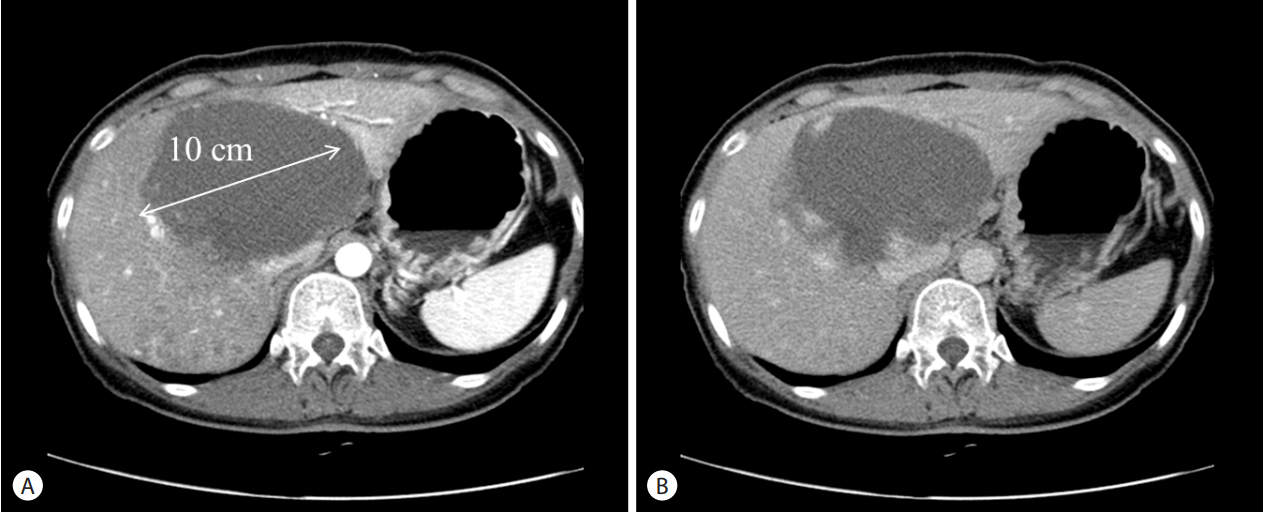

大多数肝血管瘤的生长速度非常缓慢,其增大可能与生理阶段和内分泌有关,如年龄小于30岁和妊娠期。直径小于5cm的肝血管瘤即使有少许增大一般也不会产生明显的症状和并发症,但直径大于10cm的肝血管瘤如继续增大,甚至短时间内快速增大(每年增速直径大于2cm),则可能诱发症状和并发症,需要考虑治疗。

即使肝血管瘤没有进行性增大或引起临床症状,出现以下三种特殊情况,医患双方应充分协商和权衡利弊后决定是否治疗:(1)当准备怀孕的妇女伴有巨大肝血管瘤(直径大于10cm),妊娠可能导致瘤体快速增长进而影响胎儿发育或引起破裂出血;(2)肝血管瘤巨大突出到肋弓以外且患者较瘦弱,腹部可扪及瘤体;(3)巨大肝血管瘤患者为重体力劳动者或运动员等情况。